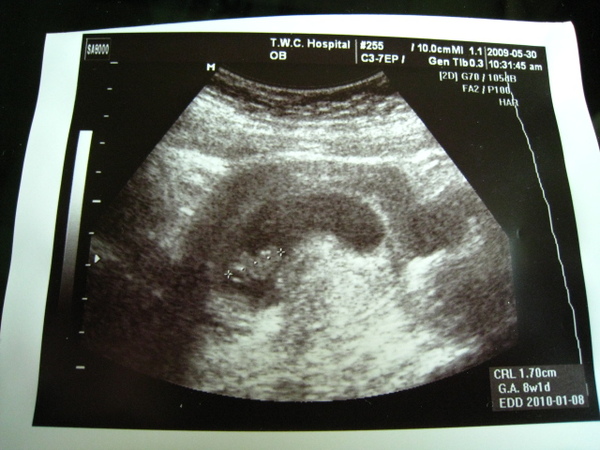

980530_8W.JPG

蕭醫生照完超音波之後,就開始跟我聊天,